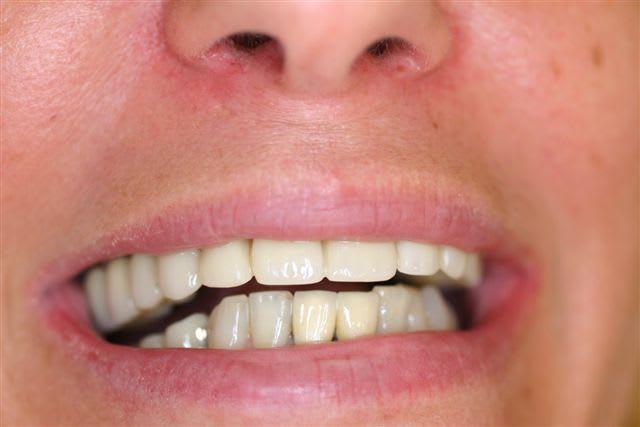

Perte d un greffon iliaque

Retraité en basale voici 6 ans avec succès